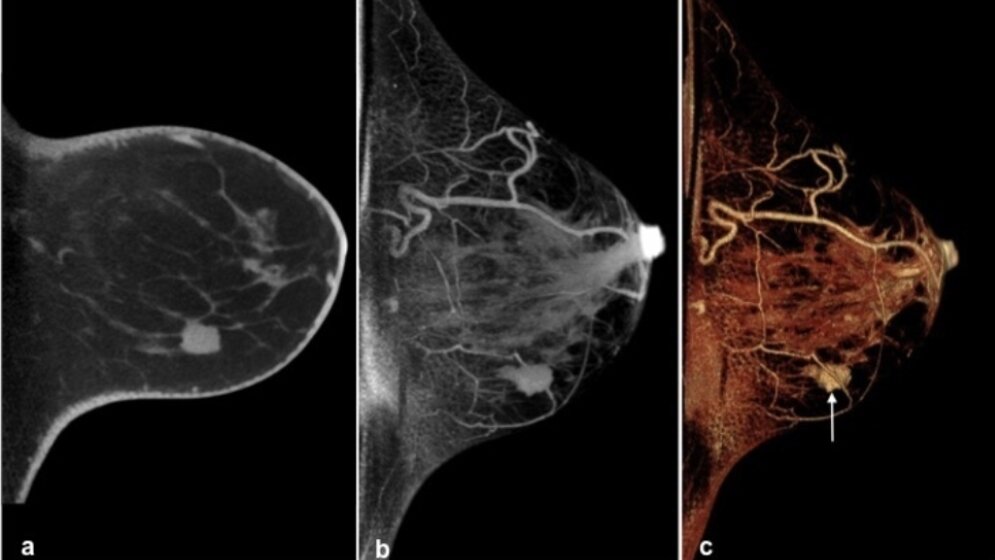

* Muzinöses Mammakarzinom links. a sagittale Einzelschicht. b Maximale Intensitätsprojektion des Datensatzes mit Mammakarzinom in den kaudalen Brustabschnitten. c Bildnachbearbeitung mit Oberflächendarstellung der intramammären Strukturen und des Tumors (Pfeil).

Eine weitere interessante Methode, die wie die Mammographie Röntgenstrahlen nutzt, ist die Tomosynthese. „Für dieses Verfahren wurde bereits im norwegischen Screeningprogramm gezeigt, dass in Kombination mit der Mammographie die Tumorentdeckungsrate gesteigert werden kann “, so Wienbeck. Die Radiologin berichtet beim Deutschen Röntgenkongress über eine Weiterentwicklung der Tomosynthese, die so genannte Kegelstrahl („Cone-Beam“)-Brust-CT. Dieses Verfahren ermöglicht, anders als die Tomosynthese, tatsächlich die Gewinnung eines dreidimensionalen Datensatzes.

Die Kegelstrahl-Brust-CT hat einige Vorteile, die die Methode künftig zu einer interessanten Option in der Brustkrebs-Früherkennung machen könnte. Zum einen lassen sich verdächtige Strukturen dank der dreidimensionalen Bildakquise präziser in allen Raumrichtungen lokalisieren. Zum anderen lassen sich Befunde sofort über eine Gewebeentnahme abklären, was den betroffenen Frauen tagelange Ungewissheit erspart. Die Methode ist für die Frauen auch angenehmer als die Mammographie, weil die Brust bei der Untersuchung nicht komprimiert werden muss.

Für ihre Pilotstudie hat die Radiologin über 100 Patientinnen mit der Kegelstrahl-Brust-CT untersucht, darunter sowohl Frauen mit bösartigen Krebserkrankungen als auch solche mit gutartigen Befunden. „Das wichtigste Ergebnis ist, dass wir mit dieser neuen Methode einen sehr hohen Anteil der bösartigen Tumoren erkennen können“, so Wienbeck. Auch bei dieser Methode gibt es aber eine gewisse Abhängigkeit von der Dichte der Brust: Die Erkennungsraten sind bei dichtem Brustgewebe geringer. Hier lässt sich die Detektionsrate durch eine Kontrastmittelgabe verbessern. Wie sich die Kegelstrahl-CT im Vergleich zur Mammographie schlägt, soll jetzt in einer größeren klinischen Studie evaluiert werden, für die die Göttinger mit Kollegen aus Norwegen und Berlin kooperieren.